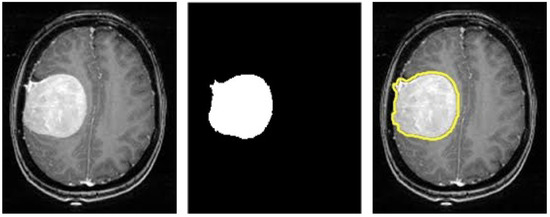

Figure 4 presents a sequence of MRI scans illustrating the detection and segmentation process of a meningioma, a type of brain tumour.

This diagrammatic representation systematically encapsulates the fusion of convolutional neural networks with sophisticated classification algorithms, crafting a comprehensive medical imaging solution. This integration aims to elevate diagnostic precision and contribute positively to enhanced healthcare outcomes. The first image on the left displays a transverse section of a brain MRI scan. It prominently shows a large, hyperintense mass in the cerebral tissue, characteristic of a meningioma. The mass appears white on the T1-weighted MRI image due to its contrast enhancement, indicating the presence of a dense, extra-axial tumour. The middle image is a binary mask highlighting the segmented tumour. This mask simplifies the image to show only the tumour region, isolated from the surrounding brain structures. Here, the tumour is depicted as a pure white area on a black background, emphasising the exact shape and boundaries of the meningioma as identified by image processing algorithms. The final image on the right reintroduces the context of the original MRI scan, overlaying a yellow outline that demarcates the perimeter of the tumour. This outline visualises the tumour’s extent and spatial relationship to nearby brain structures, crucial for surgical planning or targeted therapies. This series effectively demonstrates the application of image processing techniques in medical imaging, specifically for tumour identification, isolation, and data preparation for further clinical analysis or intervention.